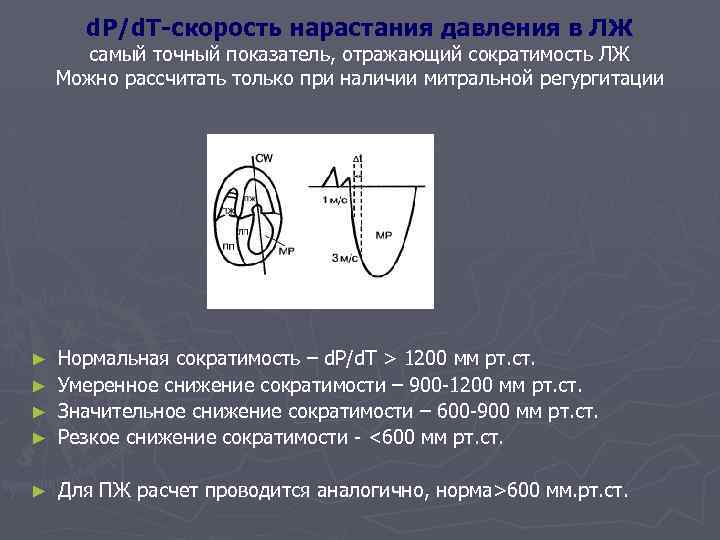

d. P/d. T-скорость нарастания давления в ЛЖ самый точный показатель, отражающий сократимость ЛЖ Можно рассчитать только при наличии митральной регургитации Нормальная сократимость – d. P/d. T > 1200 мм рт. ст. ► Умеренное снижение сократимости – 900 -1200 мм рт. ст. ► Значительное снижение сократимости – 600 -900 мм рт. ст. ► Резкое снижение сократимости - <600 мм рт. ст. ► ► Для ПЖ расчет проводится аналогично, норма>600 мм. рт. ст.